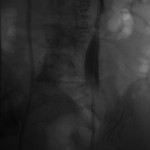

Access was gained from the back into a dilated posterior calyx of each kidney and secured with a sheath. Antegrade pyelogram on each side revealed marked ureteral and calyceal dilation due to complete obstruction of the distal ureter. A wire was advanced into the urinary bladder past the obstruction, which was dilated with a non-compliant balloon when it resisted the deployment of a nephroureteral stent. The stent was successfully deployed after the balloon dilation.

If obstructions are easy to cross, internal ureteral stents may be placed across them, with one end of the stent in the renal pelvis and the other in the urinary bladder. The stents should be changed periodically through the urethra by urologists or interventional radiologists. Sometimes, as in the patient whose images are displayed above, the obstruction must be predilated to permit insertion of the ureteral stents. Alternatively, a drainage catheter called a nephrostomy catheter can be deployed into the renal pelvis to drain urine into a bag attached to it without crossing the obstruction.

Internal ureteral stents are preferable over nephroureteral stents, which are also placed by interventional radiologists but differ from ureteral stents in having their proximal segments outside the patient, so that urine not only drains down their internal segment into the urinary bladder, but is also diverted into a bag attached to the hub of their external proximal end. They differ from nephrostomy catheters in having an internal component continuous with their external component and that runs down the ureter to the urinary bladder.